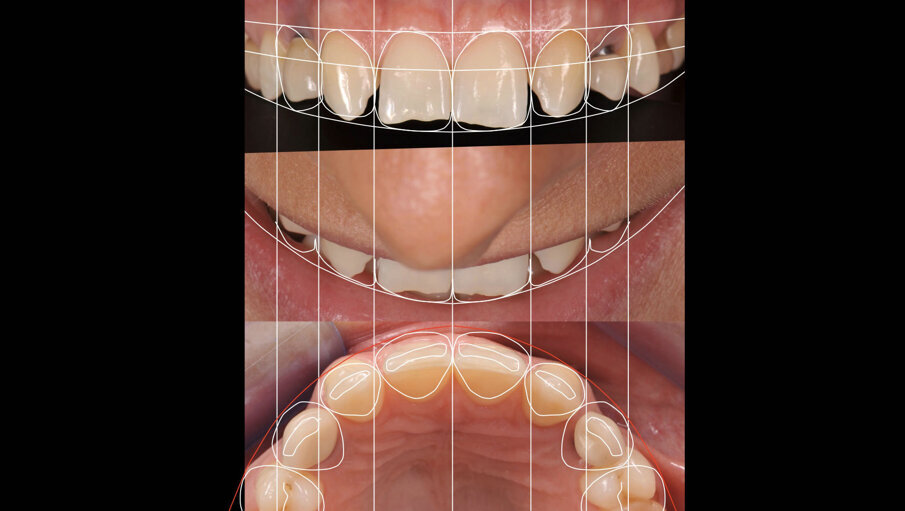

Om de behandeling niet nodeloos ingewikkeld te maken, is een set-up gemaakt waarin is gekeken of we met een restauratief/orthodontisch behandelplan uit de voeten kunnen om zo orthognatische chirurgie te vermijden. Er werd een wax-up gemaakt en deze werd met Luxatemp gepast bij de patiënte om te beoordelen of we dimensionaal goed zouden uitkomen. Deze mock-up werd ook gemaakt om patiënte te laten zien welk uiteindelijk esthetisch resultaat we zouden kunnen benaderen (afbeelding 3 en 4).

Door de regulatie van de cuspidaten naar distaal is botappositie opgetreden, waardoor bij het plaatsen van de twee implantaten een minimale botopbouw volgens een GBR-techniek noodzakelijk was (afbeelding 7-9). Via digital smile design werd de uiteindelijke vorm gesimuleerd (afbeelding 10 en 11). Er werden twee verschroefde zirkonium kronen met opgebakken porselein vervaardigd voor de implantaten en er werden facings van lithiumdisilicaat gemaakt bij de centrale incisieven en cuspidaten (afbeelding 12-17).